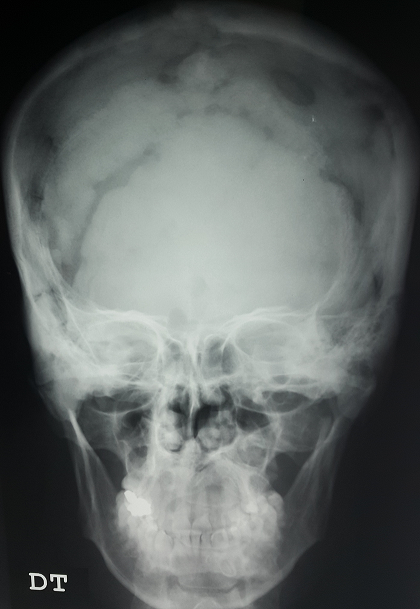

Il s'agit d'un patient de 42 ans, admis pour des céphalées fronto-occipitales évoluant depuis six semaines et devenant de plus en plus rebelles au antalgiques usuels. Le patient a comme antécédents un diabète insipide central il y a 3 ans avec insuffisance antéhypophysaire sous traitement substitutif. L'enquête étiologique initiale était négative. L'examen clinique était sans particularité. Une radiographie du crane réalisée aux urgences a révélé des lacunes osseuses diffuses. La TDM cérébrale n'a pas objectivée de lésions intraparenchymateuses. Le patient a bénéficié d'une biopsie osseuse chirurgicale qui a confirmé le diagnostic de l'hystiocytose langerhansienne. (Prolifération d'allure histiocytaire sur un fond inflammatoire avec un immunomarquage positif PS100 et CD1a). Un bilan d'extension de la maladie a révélé une atteinte fémorale gauche ainsi qu'une atteinte splénique. Les histiocytoses langerhansiennes sont des pathologies granulomateuses rares, surtout de l'enfant, d'étiologie inconnue, d'évolution et de pronostic très variable ayant en commun une lésion histopathologique comportant une prolifération et une accumulation clonale de cellules ressemblant à la cellule de langerhans d'origine myélo-monocytaire. Le tableau clinique est hétérogène et dépend de la localisation et de l'intensité de l'infiltration. Le diabète insipide central est présent chez un peu prés 40 % des patients avec atteinte systémique et peut même être révélateur de la maladie. Le traitement est nécessaire dans les formes multifocales pour réduire la morbimortalité.